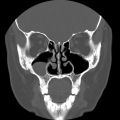

A CT Sinus exam is a fast, painless scan that captures very clear pictures of your sinus cavities. While a provider’s order is required for this exam, where you go is up to you. RAYUS centers throughout Puget Sound offer CT Sinus exams on multi-slice CT scanners run by certified technologists, typically with rates that are 30 – 50% less than if you had the same exam at a hospital-affiliated imaging provider.

The CT Sinus exam allows our subspecialized radiologists to look at different levels of the skull and sinus cavities to review for:

The CT technology allows us to see the issues behind your symptoms much more clearly than X-ray or with an endoscope, especially when evaluating the ethomid and sphenoid sinuses which sit behind the frontal and maxillary sinuses.